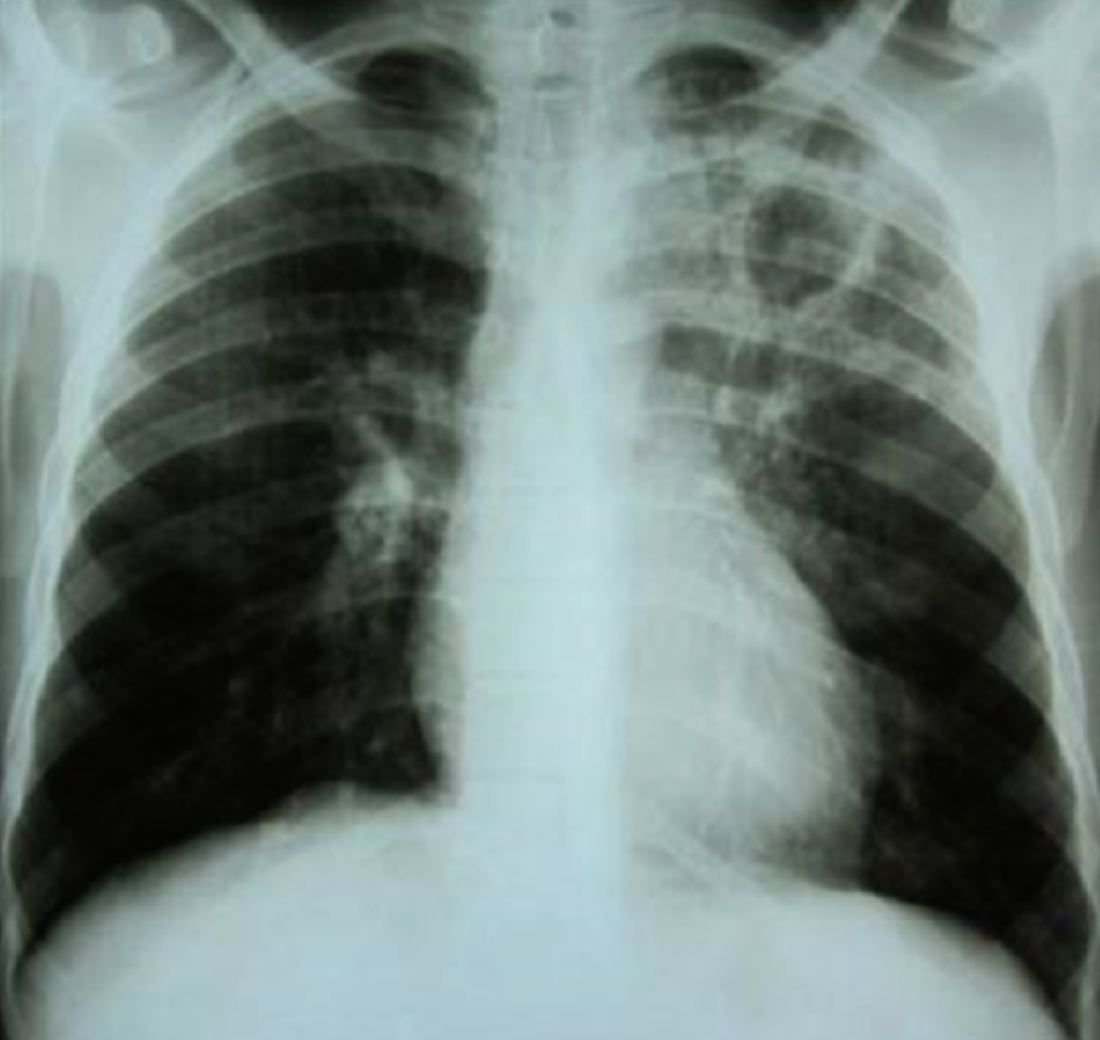

A 32 years old male presented with history of low grade fever, cough with sputum, sometimes blood stained. He has weight loss of 5 kg during this period. His chest X-Ray is shown ABOVE.

Describe the abnormality seen in the X-Ray?

- Cavitation and consolidation in the left upper lung

- bilateral Hilary lymphadenopathy

What is the likely diagnosis? Pulmonary TB

Mention 2 other investigations which you will advise?

- o Sputum culture and smear

- o IGRA

Mention 2 factors which increase the risk of this disease?

- HIV

- Chemotherapy

Mention 2 drugs used to treat this medical condition?

- o Rifampicin

- o INH (Isoniazid)